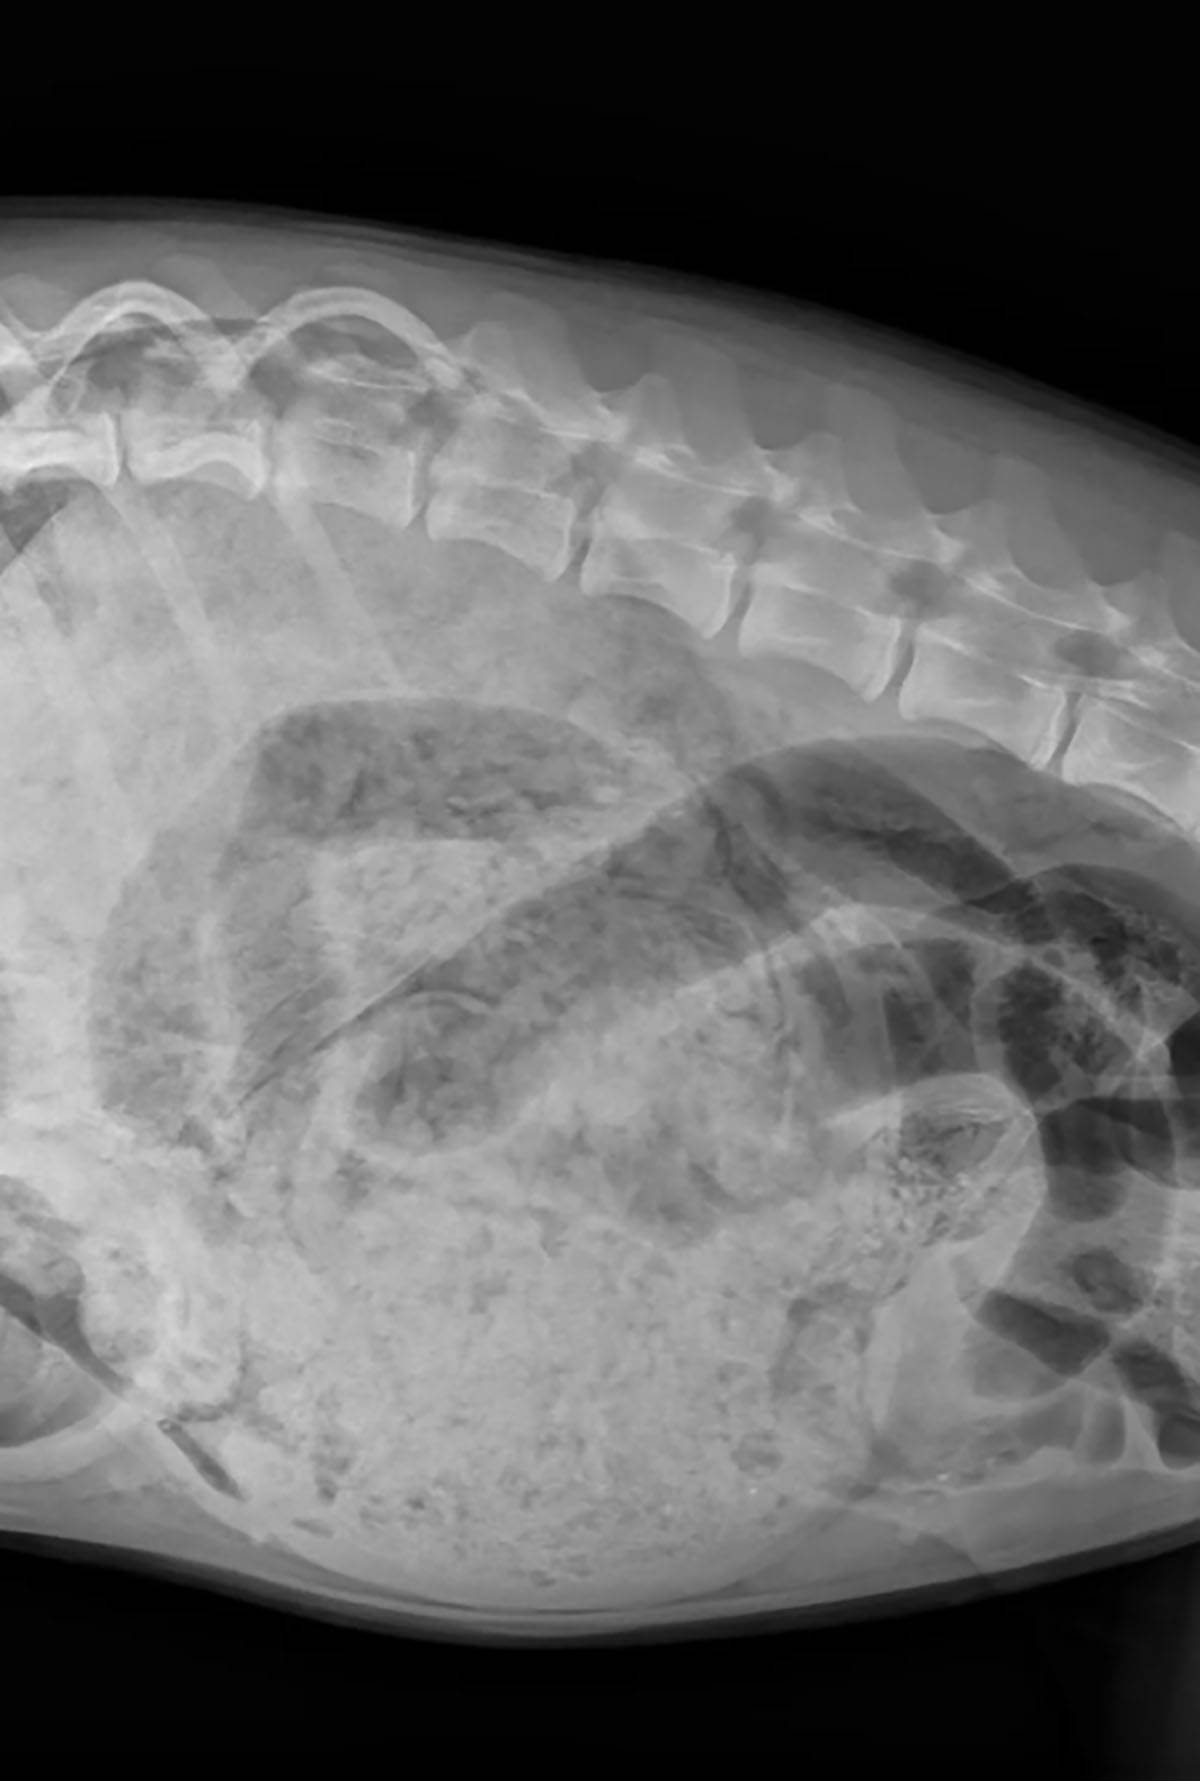

Sedmomjesečno štene po imenu Luna šokiralo je sve u ambulanti kada su ga vlasnici dovezli jer mu je pozlilo.

Mlada ženka rase bernski planinski pas, po imenu Luna, oporavlja se od više hirurških zahvata nakon što su veterinari u Los Anđelesu pronašli desetine predmeta u njenom stomaku.

7-mjesečna Luna oporavlja se od obimne procedure, nakon što je njen veterinar iz stomaka izvadio 24 čarape i još nekoliko drugih predmeta.

Prema objavi na Instagramu Centra za hitnu pomoć za životinje u Koroni, koji se nalazi 50 milja van Los Anđelesa, Luna je hitno dovedena u bolnicu nakon što su njeni vlasnici primijetili da povraća i da ima "čvrst, naduven stomak."

"Ono što smo pronašli bilo je nevjerovatno", napisala je bolnica, uz rendgenske snimke Luninog stomaka punog odjeće, kao i fotografije njenog oporavka i snimak veterinarke, dr Dženi, koja pozira sa svim stvarima koje su pronađene u njenom stomaku - uključujući "24 čarape, dvije gumice za kosu, jedan uložak za obuću, jedan mali kombinezon (iz njenog crijeva!) i razne komade tkanine."

Veterinarska klinika je potvrdila da je Luna prošla kroz gastrotomiju kako bi očistila svoj stomak i enterotomiju kako bi uklonila kombinezon, koji je izazivao opstrukciju crijeva.